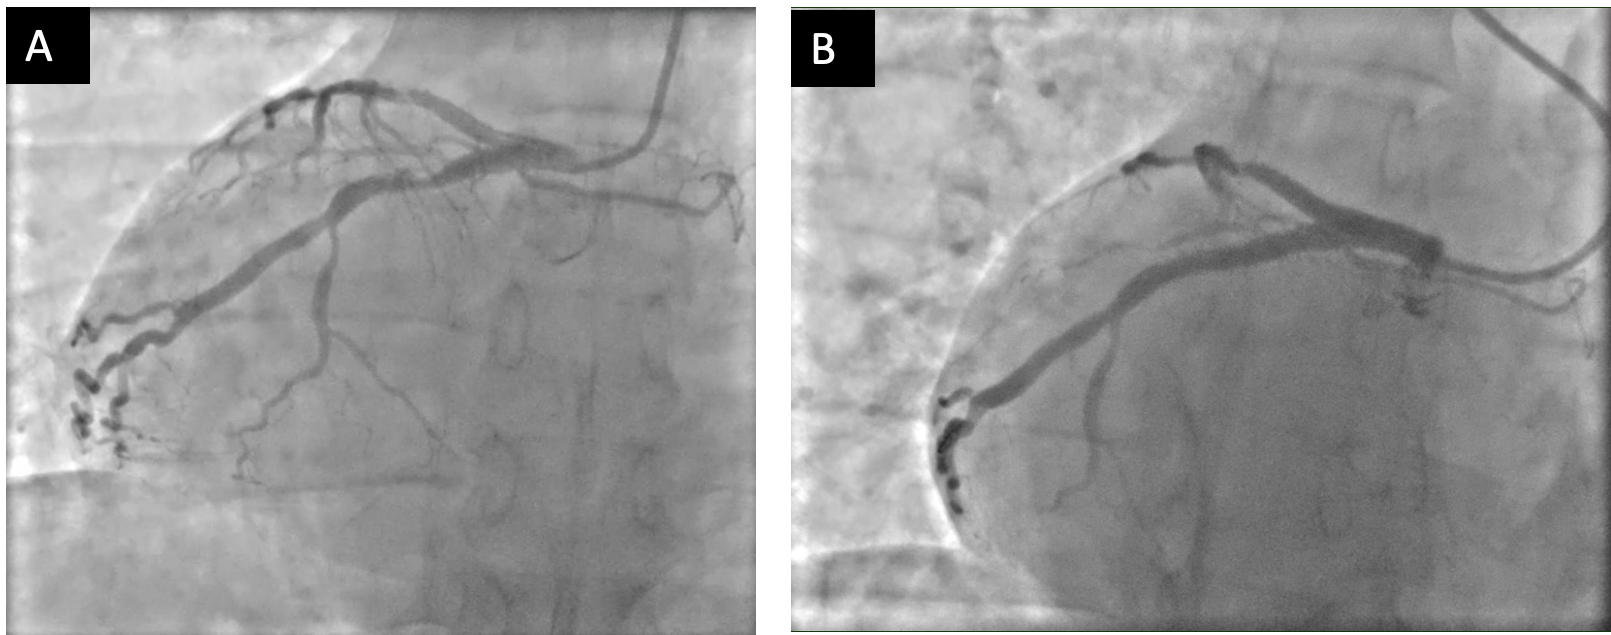

A 49-year-old male with a medical history of dextrocardia, hypothyroidism, dyslipidemia and hypertension was referred to a cardiologist by his primary physician due to a 3-week history of unstable angina. His vital signs were normal, and the physical examination was unremarkable. Electrocardiogram (ECG) showed a prominent S wave in the left-sided leads and a prominent R wave in the right-sided chest leads, suggesting dextrocardia. Although he had a normal echocardiogram and stress test a year ago at a different hospital, due to his symptoms and intermediate-high risk probability of coronary artery disease (CAD), the decision was made to proceed with a cardiac catheterization using a trans-radial approach with a horizontal sweep technique. During the procedure, a 6-French tiger catheter (TIG) was guided into the left coronary sinus and advanced into the left ventricle under fluoroscopic guidance.

The left main coronary artery was widely patent bifurcating into the left anterior descending and left circumflex. The left circumflex had 80% proximal stenosis with minimal luminal irregularities in the mid to distal portion. After guidewire crossing, balloon angioplasty was performed, and a drug-eluting stent was deployed. An intravascular ultrasound was also performed, which was negative for vessel dissection. There were no post-procedure complications, and the patient was discharged on beta blockers and dual antiplatelet agents.